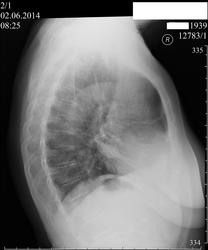

Пациентка 74 лет. Проходила проверочную флюорографию.Предъявляет жалобы на головные боли.Назначено дообследование R-графия лёгих в прямой и првой боковой проекции.

Посчитаю образованием правого лёгкого.В синусе вроде бы жидкость(не уверен).Среагировала междолевая.

Считаю, что тень обусловлена осумкованным междолевым плевритом

+1. Я то же  в заключении написал, что больше данных за междолевой плеврит. Смотрел пациентку на R-скопии: не сложилось впечатления , что окрулгая тень находиться в лёгочной ткани, скорее имеет отношение  к междолевой плевре.Не нашёл данных за выпот в плевральной полости. По сути пациентка не предъявляет лёгочных жалоб: ни одышки, ни болей в грудной клетке нет ( хотя вроде бы, следовало их ожидать...).Пациента госпитализирована лёгочное отделение, считаю, что для уточнения диагноза показана КТ лёгких.

При первичном осмотре похоже на выпот, но,обычно, междолевая щель не просматривается на фоне осумкованного выпота. Здесь она хорошо видна. См. рисунок.

Добрый вечер, Nikolas! Сомнения есть. Возможно вы правы, в том плане, что при осумкованном выпоте междолевая щель не должна быть видна, могу предположить, что это правло работает при больших объёмах выпота, в данном случае, если он ( осумкованный выпот) есть то в небольшом объёме.Думаю, что КТ должна расставить точки над i.

Выполнена линейная  томография.Заключение: округля тень прилежит к главной междолевой плевре справа в базальном отделе, обусловлена организовавшимся междолевым плевритом или фибротораксом. Надеюсь, что сами изображения смогу выставить в ближайшие дни.